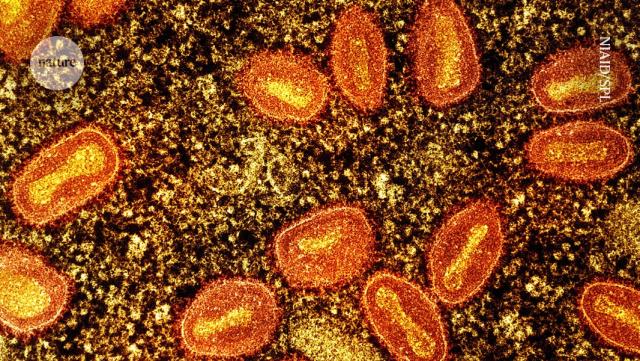

Mpox is spreading rapidly. Here are the questions researchers are racing to answer

Mpox clade II has been spreading since 2022. Mpox clade 1 has 2 cases outside the endemic area in central Africa.

nature.com/articles/d41586-024…

Mpox is spreading rapidly. Here are the questions researchers are racing to answer

Nature talks with infectious disease specialists about whether vaccines will curb this outbreak and more.Reardon, Sara